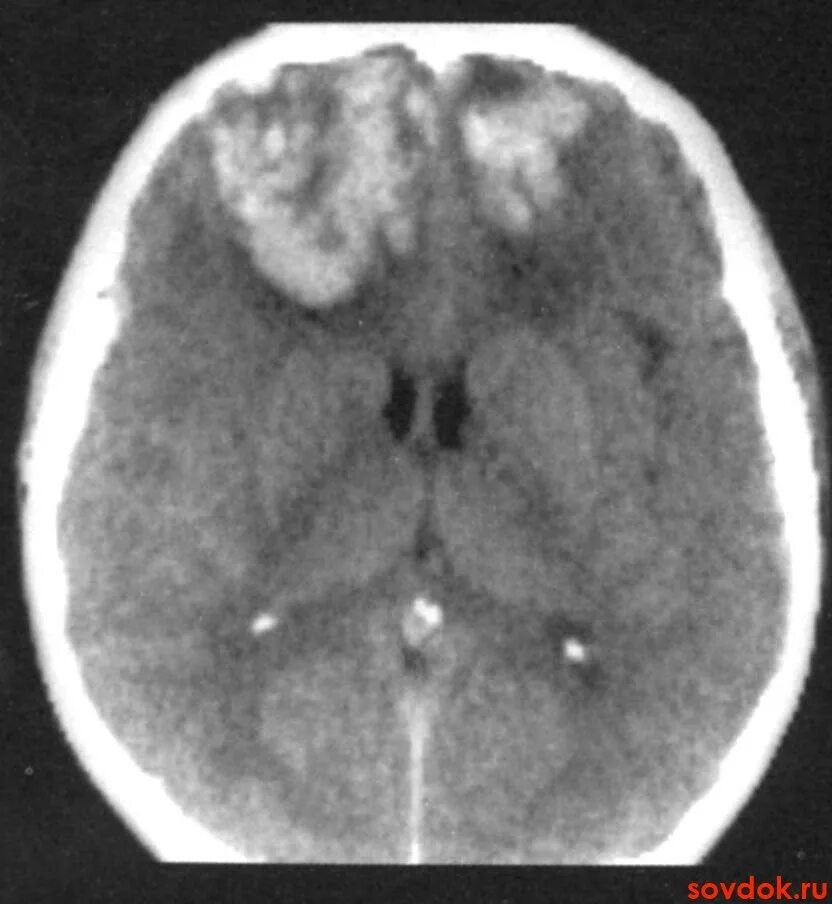

Ушиб головного мозга кт